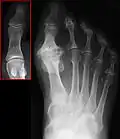

Die Diagnose kann durch die klinische Untersuchung gestellt werden. Typisch ist die eingeschränkte Beweglichkeit vorwiegend in der Dorsalextension, oft sind am Köpfchen des ersten Mittelfußknochens dorsale und auch mediale Knochennasen (Osteophyten) zu tasten.

Gelegentlich finden sich auch Entzündungszeichen in Form von Rötung, Schwellung und Erwärmung. Im Röntgenbild (Abbildung links) findet sich eine Verschmälerung des Gelenkspaltes – bis hin zur Aufhebung. Ursache ist Abrieb des Knorpels. Weiter finden sich Ausziehungen an den Gelenkflächen.